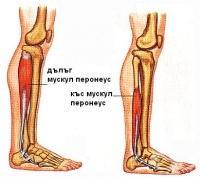

S86.3 Травма на мускул(-и) и сухожилие(-я) от групата на перонеуса на ниво подбедрица

Перонеалната мускулна група е изградена от: m.peroneus longus и m.peroneus brevis. Травма на мускул(...